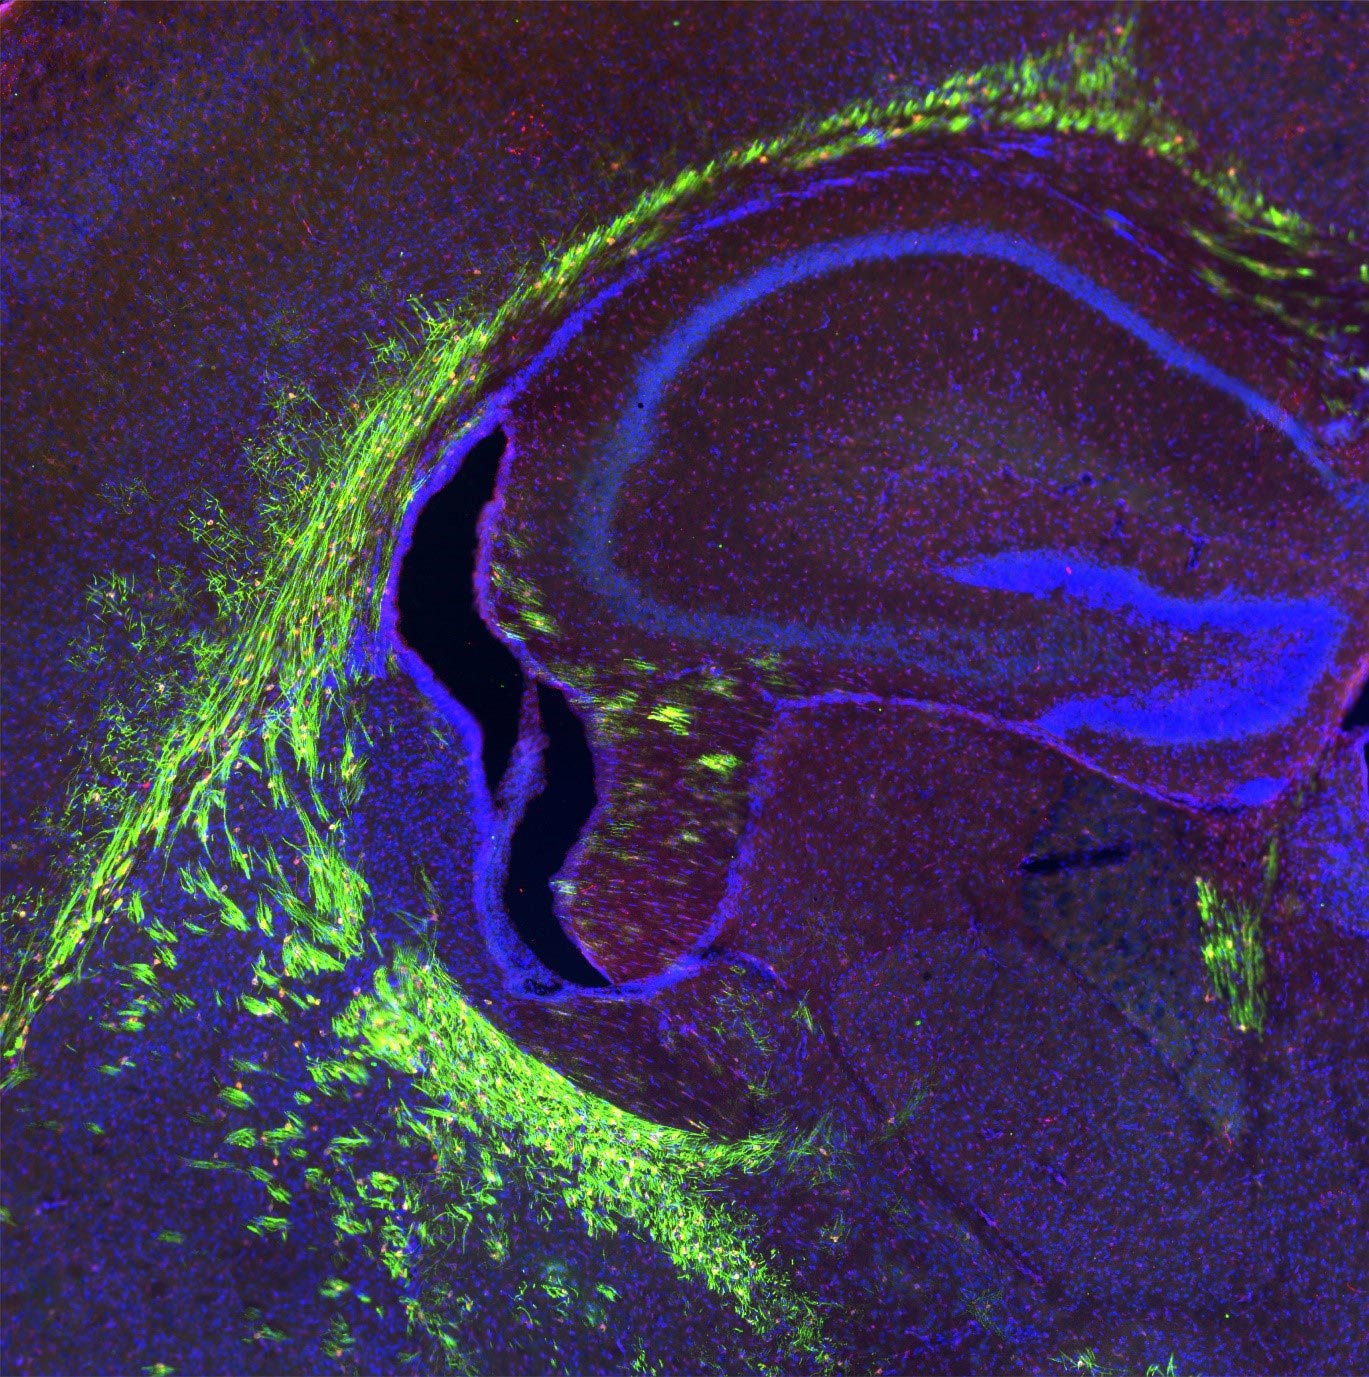

A study from Ohio State University has found that high-fat diets can negatively impact memory formation, particularly in aging mice. The research identified the omega-3 fatty acid DHA as a potential defense against the brain inflammation caused by high-fat diets. The study focused on microglia and hippocampal neurons, finding that palmitic acid from high-fat foods induced increased inflammation in both cell types. However, pre-treatment with DHA had a protective effect against inflammation. The study also revealed that a high-fat diet in aging mice disrupted specific brain cell signaling, hindering the creation of new memories. This research provides insights into how fatty foods affect brain cells and memory, especially as we age.